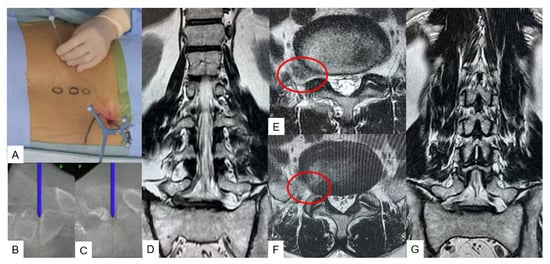

3.2.2. C-Arm-Free Biopsy [13]